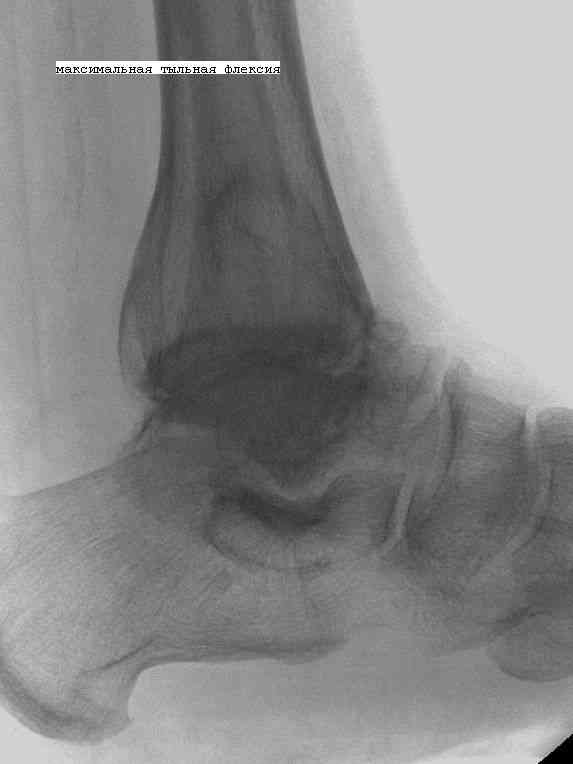

Эндопротезирование или артродезирование ?К нам обратился пациент 73 лет с жалобами на боли и деформацию в области левого голеностопного сустава. В анамнезе: в 1980 году перелом обеих лодыжек с вывихом стопы кнаружи. Лечился консервативно: одномоментная репозиция переломовывиха в левом голеностопном суставе с трансартикулярной фиксацией голеностопного сустава спицами Киршнера через пяточную, таранную, большеберцовую кости. Накладывалась гипсовая иммобилизация. Даная манипуляция осложнилась нагноением с развитием гнойного артрита. Были удалены спицы, сустав со слов больного, промывался растворами, но не вскрывался, получал антибиотики. Гнойный процесс был купирован, и рецидива с тех пор не было.Об-но: Левый голеностопный сустав деформирован за счет разрастания костной ткани и отечности мягких тканей. Левая стопа с вальгусной установкой, практически отсутствуют все своды левой стопы (стопа плоская). Полный объем движений в левом голеностопном суставе максимум достигает 15 гр, движения стопы в основном за счет подтарнного сустава. Пальпаторно область голеностопного сустава не столь болезненна, как болезненна область подтаранного сустава и область таранно-ладьевидного сустава.После изучения объективного статуса, анамнеза, рентгенснимков, больному предложен был трехсуставной артродез, так-как мы сочли это наиболее приемлемым в данном случае. Но больной отказывается от данной операции и настаивает на эндопротезировании левого голеностопного сустава. Во первых, наше отделение не имеет опыта в эндопротезиовании голеностопного сустава. Во вторых, нам кажется, что трехсуставное артродезирование в данном случае наиболее подходящее. Причиной тому, на наш взгляд, выраженная деформация левой таранной кости, как следствие аваскулярного некроза, и то что болит не голеностопный сустав в данном случае ( хотя в нем и ограничено движение), а подтранный и таранно-ладьевидный суставы и то что эндопротезирование одного голеностопного сустава не решит проблем в подтаранном, ладьевидно-таранном сочленениях. Наши доводы оказались безуспешными, а так как пациент является ученным, требовал доказательной базы наших умозаключений. Ваше мнение по данному случаю, и мы были бы благодарны, если у кого то есть материал по данной теме или есть ссылки. Заранее благодарны всем, кто примет участие в обсуждении данной темы.